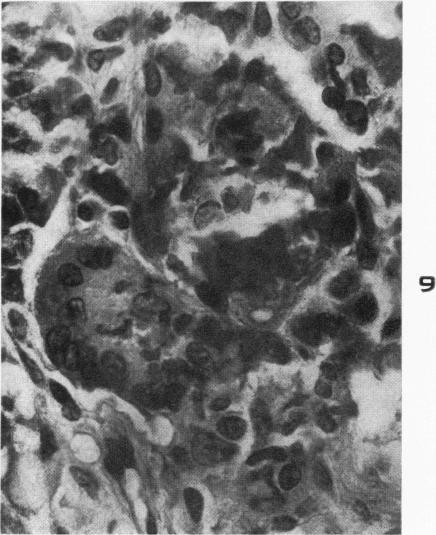

ARONSON S M, SHWARTZMAN G

Am J Pathol. 1956 Mar-Apr;32(2):315-33.